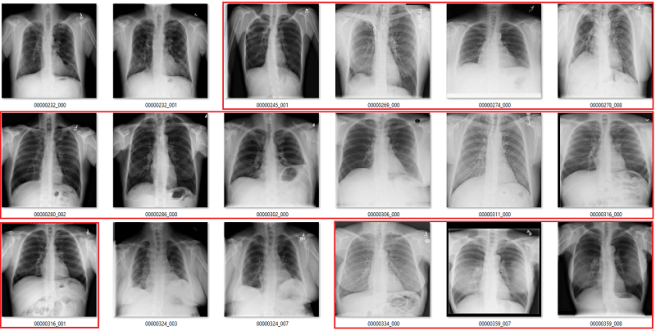

What follows is a bunch of pictures based on the labels in the dataset. In this case, they are pseudo-random. Like I said, it doesn’t have to be perfect. They are randomly chosen sequential sets of 18 images. They are not cherry-picked.

Also, I have tried to err on the side of caution, in the sense that I favour the label class when a case is equivocal.

In all the images, red = clearly wrong label. Orange = I doubt it, I wouldn’t report it, but I can’t really exclude it. Correlate clinically :p

Atelectasis

Fibrosis

My labels aren’t perfect. Other radiologists will disagree with some of them, and the reduced resolution doesn’t help. But it should be clear that my labels and the results presented in the paper/supplement are vastly different.

I always like hard numbers, so I did my best to quantify the label accuracy where I can. I actually found it very hard to define many of the labels, which is why they are not listed below. I reviewed ~130 images in each class, and calculated the accuracy of the original labels according to my visual interpretation. This is a pretty good amount of data to use, as the 95% confidence intervals will probably be less than +/- 5%, even allowing myself up to a 20% error rate.

Visual analysis by me. Text mining results from the paper.

Again, I doubt my labels are “right” compared to some form of fairly reliable ground truth (like a panel of chest radiologists), but the difference here is stark. I think that these findings make a strong case that these labels do not appear to visually match the diseases they should represent.